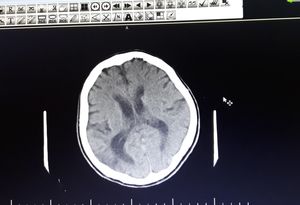

81 year old male with history of CVA 3 years ago, now referred with generalized weakness and quadriparesis and dysartheria and verbal agression from 1 month ago.

Are ventricles in normal size ?

Hydrocephalus....maybe non-obstructive?